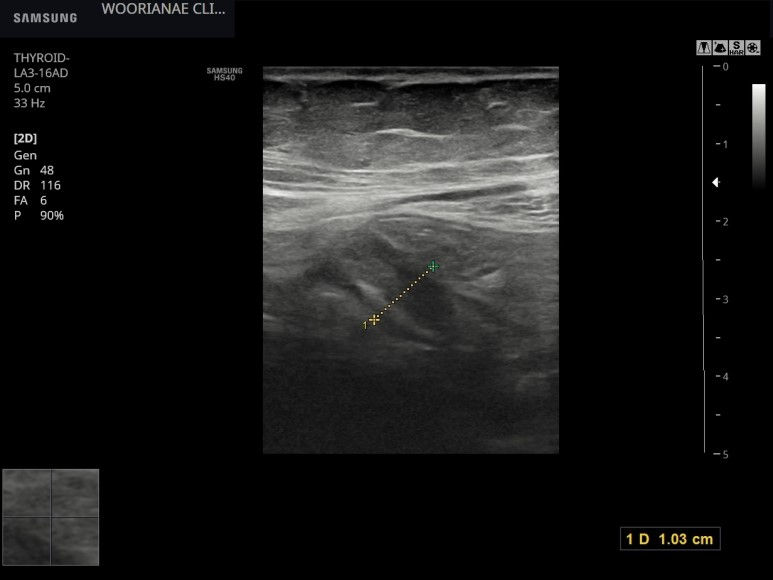

타원 CT에서 간암 소견, 재확인 위해 내원, 간암 (HCC) 의 초음파 소견

60대 후반 여자 약 10년간 B형 간염 항바이러스 약제 복용 중 최근 초음파에서 종괴 보여, CT에서 간암 소견 확인, 이전 초음파에서는 정상 소견이었다고 함 재확인 위해 내원 실질은 거칠지만 간 표면은 매끈한 편이었으며 간문맥 혈류...